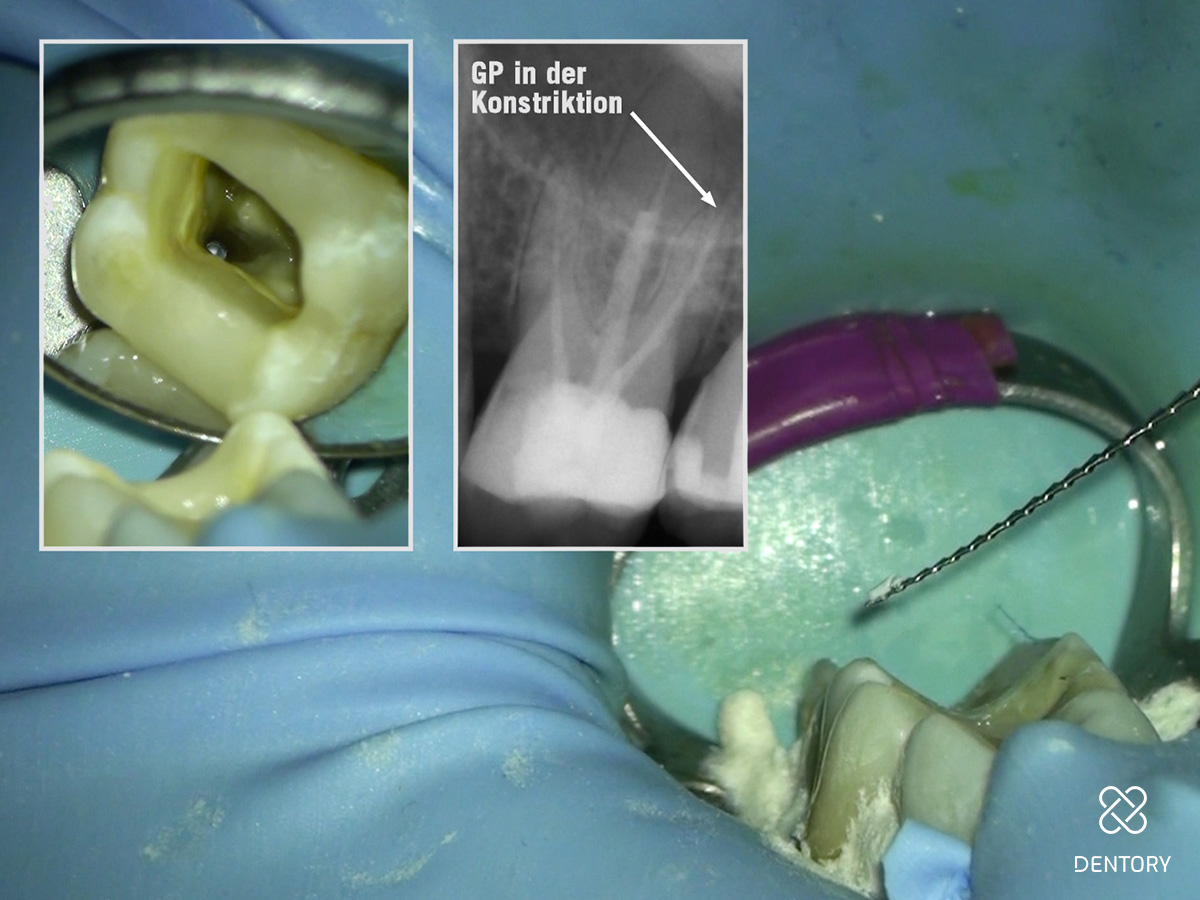

Abbildung 7

Maschinelle Guttapercha-Entfernung: Entfernung der koronalen Guttapercha mit einer Revisionsfeile nach vorherigem Aufweichen der Guttapercha mit Orangenöl. Die restliche Aufbereitung erfolgt mit NiTi-Feilen.

Abbildung 8

Händische Guttapercha-Entfernung: Entfernung der Guttapercha, die über die Konstriktion hinaus geht mit einer Hedström-Feile ISO 25.